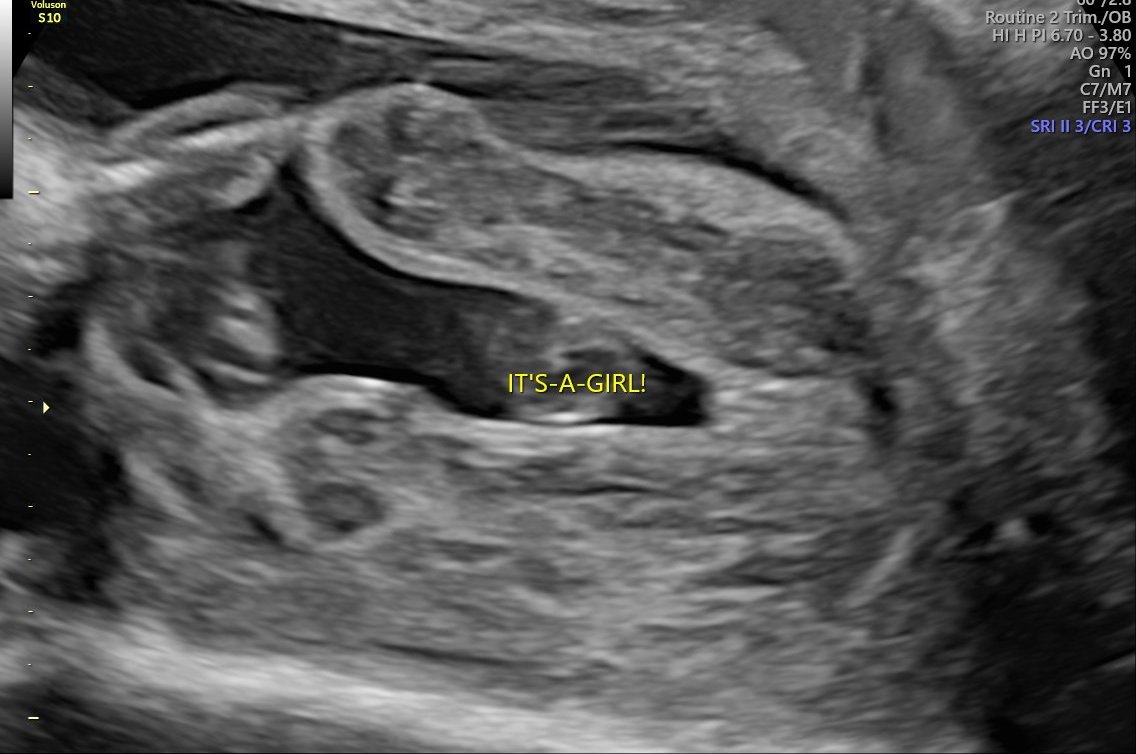

Минах и аз втората фетална,доктора каза момиче на 200% 🌸. В 22г.с съм и бебка тежи 509 гр. Бях накупила малко дрешки за момче,но ще трябва да ги върна ,добре че пазя бележките. 😆 Термина ми засега е 23.08 💓